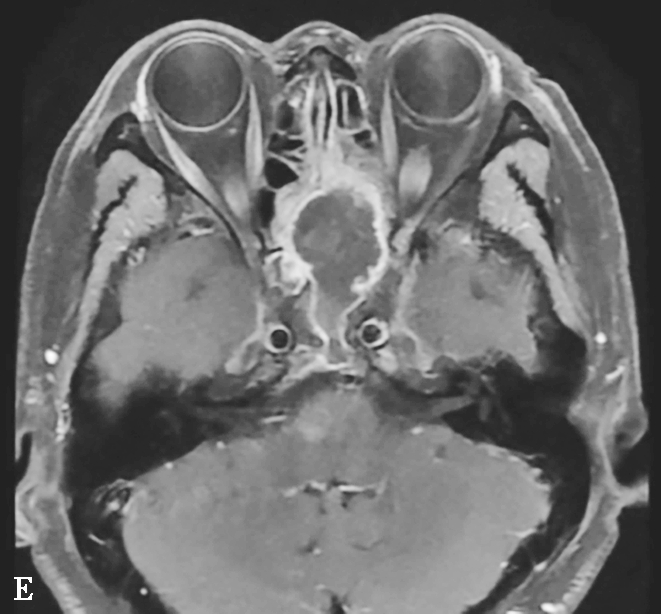

2.MRI表现

T 1 WI多为低或等信号,T 2 WI多为高信号,增强后有明显强化。MRI能更清楚显示眼眶、颅内、海绵窦等鼻外蔓延范围,为治疗方案选择提供依据,对术后随访也有很大帮助(图1-3-23C~E)。

图1-3-23 急性侵袭性真菌性鼻窦炎

A、B.横断面、冠状面CT骨窗,示双侧蝶窦、后组筛窦软组织影,密度不均,窦壁骨质硬化伴局部骨质破坏,累及双侧圆孔、翼管;C~E.MRI横断面T 1 WI、T 2 WI、T 1 WI+FS+C,示双侧蝶窦、后组筛窦内混杂长T 1 、长T 2 信号,窦腔内见斑片状短T 1 、短T 2 信号影,增强扫描边缘强化,前颅底脑膜增厚强化